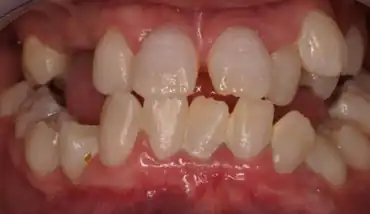

Type I: Radicular type

Type I has been known as radicular dentine dysplasia because the teeth have undeveloped root(s) with abnormal pulp tissue. Morphology and colour of the crown mostly appear normal, but occasionally teeth appear slightly amber coloured or bluish-brown shine in primary teeth with no or only immature root development. The teeth are mostly maligned and have higher risk of fracture.[12]

Radiographic feature

In other words, affected primary teeth usually have abnormal shaped or shorter than normal roots. “Crescent/half-moon shaped” pulp chamber remnant in permanent teeth can be seen on x-rays. The roots may appear to be darker or radiolucent/pointy and short with apical constriction. Dentine is laid down abnormally and causes excessive growth within the pulp chamber. This will reduce the pulp space and eventually cause incomplete and total pulp chamber obliteration in permanent teeth.[12][13] Sometimes periapical pathology or cysts can be seen around the root apex.[11] Most cases of DD associated with peri-apical radiolucency/ pathology have been diagnosed as radicular cysts, but some of them have been as diagnosed peri-apical grauloma instead.[14]